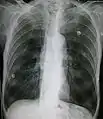

مقطع بالصدر بالتصوير الطبقي المحوري

حالة متقدمة من انتفاخ الرئة